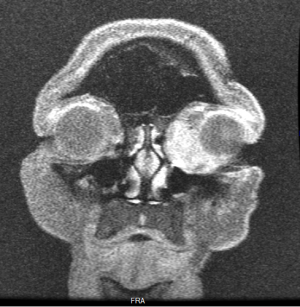

Given the difficulties of assessing lacrimal sac papillomas with external exam, imaging studies are an important component of their diagnosis and evaluation of their extent. Smooth masses can be seen on CT or MRI, with a characteristic heterogeneous signal on the latter being useful for differentiating from more homogenous lymphoid tumors. More broadly, dacryocystography can also be used to reveal the presence and location of lacrimal sac masses like papillomas, which can show up as a characteristic protruding defect in tumors extending into the lumen, though this is not a widely used study.